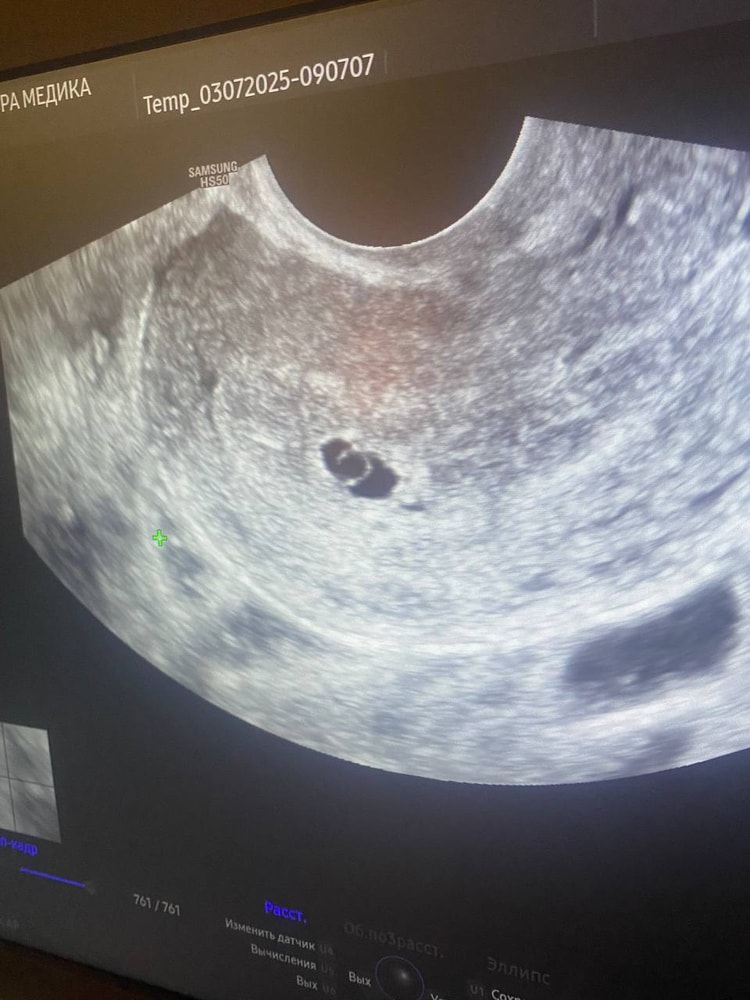

Юлия *, есть еще фото. Я тут вообще эмбриона не вижу

Екатерина , кстати по узи видно да, что она напутала что-то

Зоя Асташова, вот только что пришло в голову, а не пропустила ли узистка цифру 1 перед 5 в размерах плодного яйца. Послала дочь уточнить и действительно сдв плодного яйца 15,6 а не 5,6 🙏в этом случае все неплохо и уже скоро появится сердцебиение

Екатерина , ааа, ну логично, даже по картинке видно - если бы и правда пя 5,6, то жм со своим размером должен почти полностью его занимать! А там ещё два таких поместятся😆